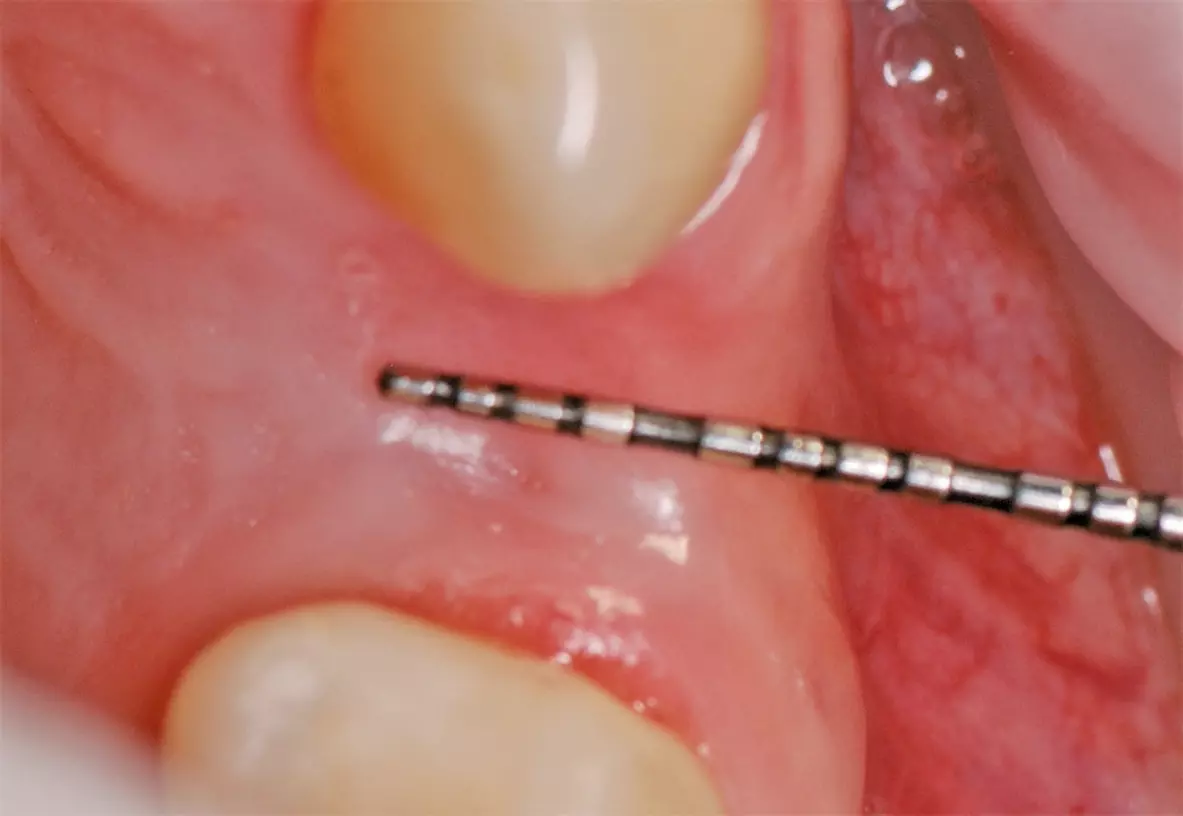

Nach schonender Extraktion des Zahnes 24 unter Erhalt der vestibulären Lamelle wurden die PRF-Plugs in die Extraktionsalveole eingebracht (Abb. 14 und 15) und mit einer Naht fixiert (Abb. 16). Am ersten postoperativen Tag zeigte sich die Wunde reizlos und Fibrinbelegt (Abb. 17). In der ersten postoperativen Woche war die Patientin beschwerdefrei und hatte nicht von ausgeprägten Schwellungen oder Schmerzen berichtet. An Tag 7 war die Wunde vollständig geheilt und mit gesunder Gingiva überdeckt. Eine leichte Mulde von etwa 1 mm war noch zu beobachten (Abb. 18). Nach drei Monaten zeigten sich gesunde Weichgewebsverhältnisse, sowie ein weitgehend erhaltener Alveolarkamm mit leichter vestibulärer Einziehung (Abb. 19).